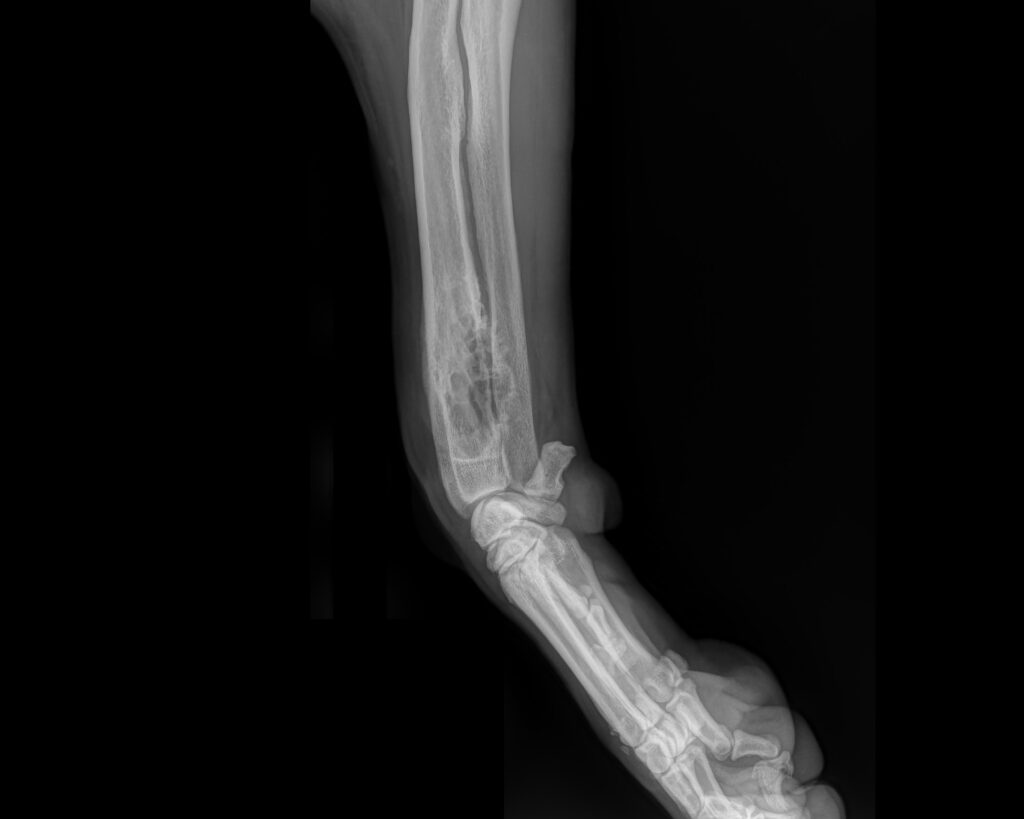

Monty’s bilateral antebrachial growth deformity

PATIENT STORY